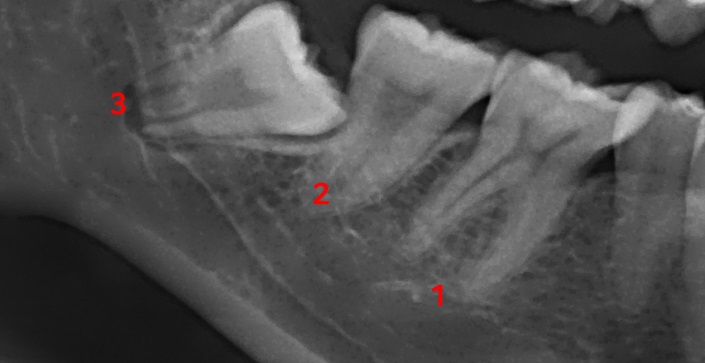

위 사진은 예전에 제가 사랑니를 뽑기 전에 찍었던 엑스레이 사진의 일부입니다. 이해를 돕기 위해 첨부해보았습니다. 사진에서 보다시피 한쪽에 큰 어금니는 사랑니까지 3개가 있습니다. 양쪽 위아래 사랑니가 모두 있다면 구강 내에 큰 어금니는 총 12개가 되겠죠? 사진에 표시한 1번이 제1 대구치, 2번이 제2 대구치라고 부릅니다. 사랑니는 사진에 표시한 3번, 제3 대구치입니다. 제일 안쪽에 있는 세 번째 큰 어금니입니다. 사랑니는 위, 아래 모두 다 맹출 했다면 총 4개가 있을 것이고 3개, 2개, 1개만 있는 분들도 있고, 아예 맹출 하지 않는 분들도 있습니다. 또 사랑니가 나는 형태와 크기도 사람마다 제각각입니다. 똑바로 맹출 하는 경우도 있고 누워서 나는 경우도 있습니다. 사랑니는 보통 고등학생 이후로 나기 시작합니다.